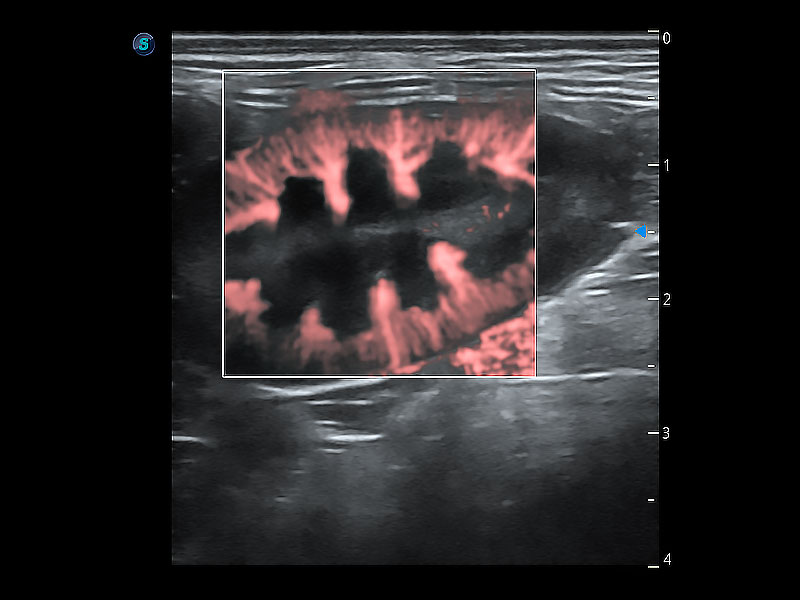

高性能和先进的临床应用工具可以为动物医生提供临床信心。ProPet 80 搭载了先进的腹部和浅表应用工具,帮助医生在日常临床实践中发挥前所未有的作用。

极大提升超低速微细血流的检出能力,同时更精准地滤除软组织和超声信号,为兽用医生提供以往无法通过常规血流获得的疾病诊断信息。

为精细结构及组织边缘提供高清晰度的图像和更大的成像视野。帮助减轻医生的用眼疲劳,快速精准获得测量的数据。